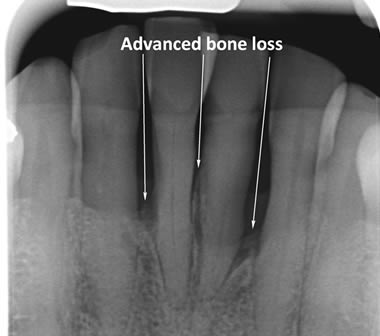

Periodontitis is a more advanced stage of gum disease where there has been damage to the bone which supports the teeth. If left untreated periodontitis leads to more and more bone loss until the teeth start to become loose and eventually fall out by themselves or need to be extracted by a Dentist.

The main cause of gum disease is plaque. Plaque consists of millions of bacteria which live on and around the teeth and gums. These bacteria produce toxins which damage the gums. To begin with the gums start to peel away from the teeth and “pockets” form. As the bacteria penetrate deeper into these “pockets” they then start to cause damage to the bone which holds the teeth in. As more bone loss occurs the teeth start to become increasingly looser until they eventually start to fall out one by one.

The diagrams below show the different stages of gum disease